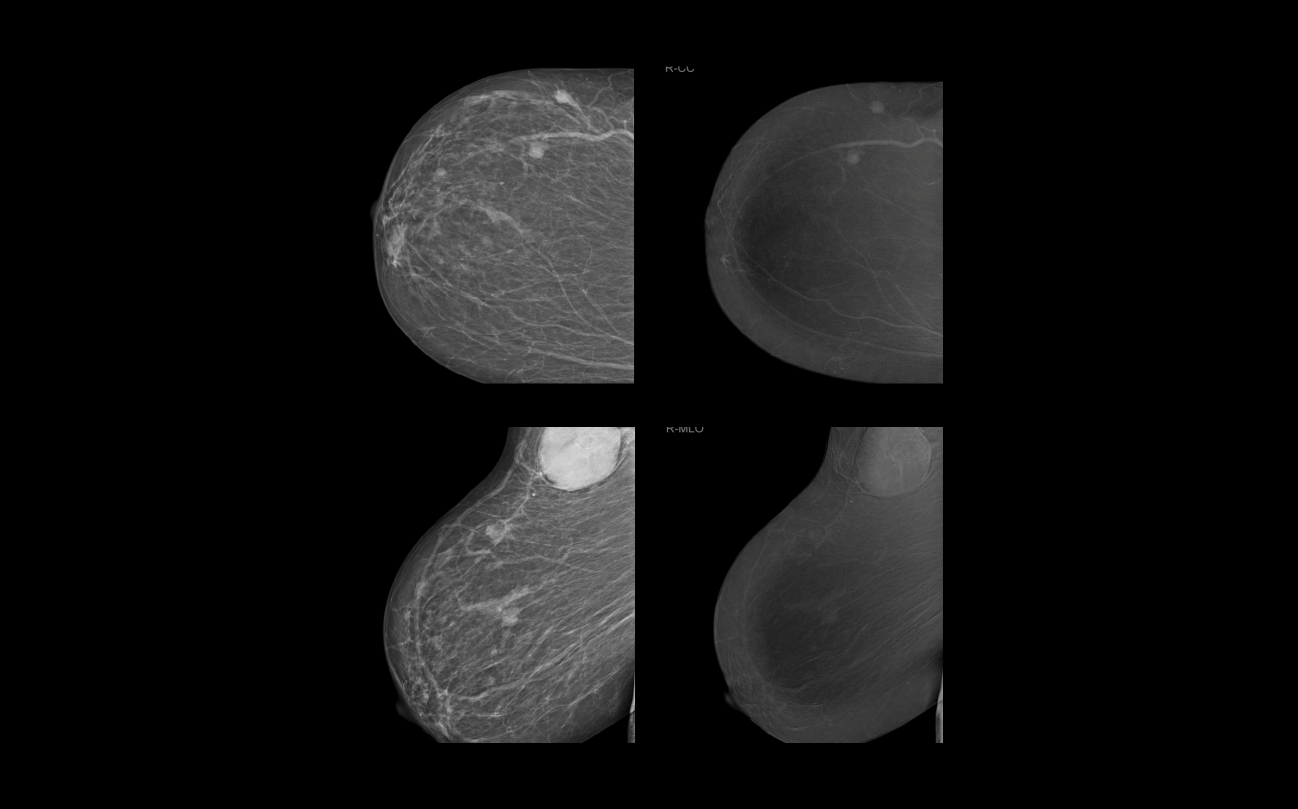

The patient is a 55-year-old female patient with a known history of carcinoma. The mediolateral oblique (MLO) standard mammographic views delineate the IDC from the previous examination. The initial plan was to do a conservative surgery. Further imaging with CEDEM prospective assessment revealed multiple non-palpable small nodules and enhancement in high energy contrast imaging. Late enhancement images outlined the axillary masses with adjacent lymph nodes. IDC was confirmed by the biopsy and other advanced imaging techniques which led to the decision of other clinical management in place of the surgical plan.